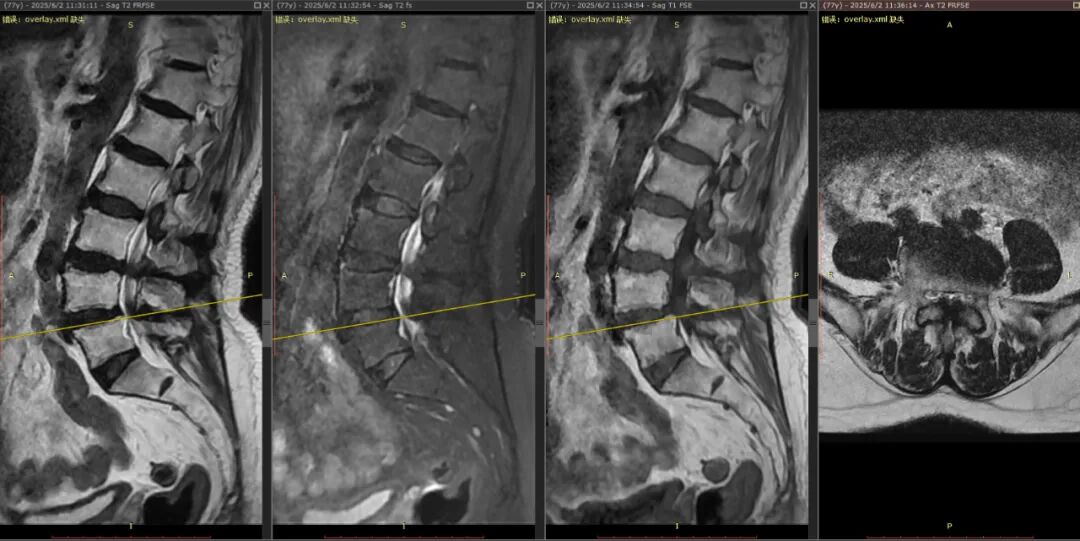

接诊后,周大爷的核磁共振结果让医生们也倒吸一口凉气:他的两节腰椎管已极度狭窄,神经结构几乎被挤压到无法分辨,手术难度和风险极大。

经过周密评估,曾小军团队为周大爷量身定制了“椎间孔镜下单侧入路双侧减压+骨水泥强化椎弓根钉内固定”的手术方案。曾主任通俗地解释道:“这好比一条被淤泥堵塞的河道。我们只需通过一侧一个不足1厘米的切口,就能在内镜的辅助下,为双侧受压的神经‘清淤拓宽’,精准解除压迫。同时,用骨水泥加固螺钉,就像给老化的骨骼‘焊接钢筋’,确保脊柱在减压后依然稳固。”